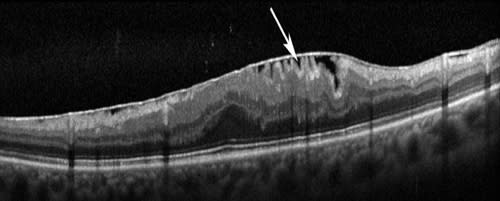

Figure 1. SD-OCT scans showing the difference between vitreomacular adhesion and vitreomacular traction.

Top image shows attachment of posterior hyaloid (arrow) without any distortion of normal foveal contour suggestive of vitreomacular adhesion; this is a very normal configuration in older eyes.

Bottom image shows posterior hyaloid (arrow) with distortion of foveal contour with cystic changes and splitting of retina suggestive of vitreomacular traction.